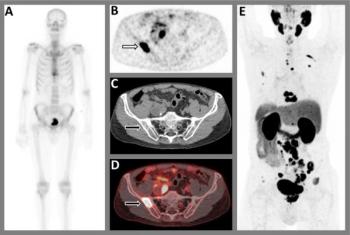

Researchers showed that adjunctive use of a deep learning algorithm resulted in an eight percent increase in sensitivity and a nearly 10 percent increase in specificity for differentiating between colon carcinoma and acute diverticulitis on computed tomography (CT) scans.